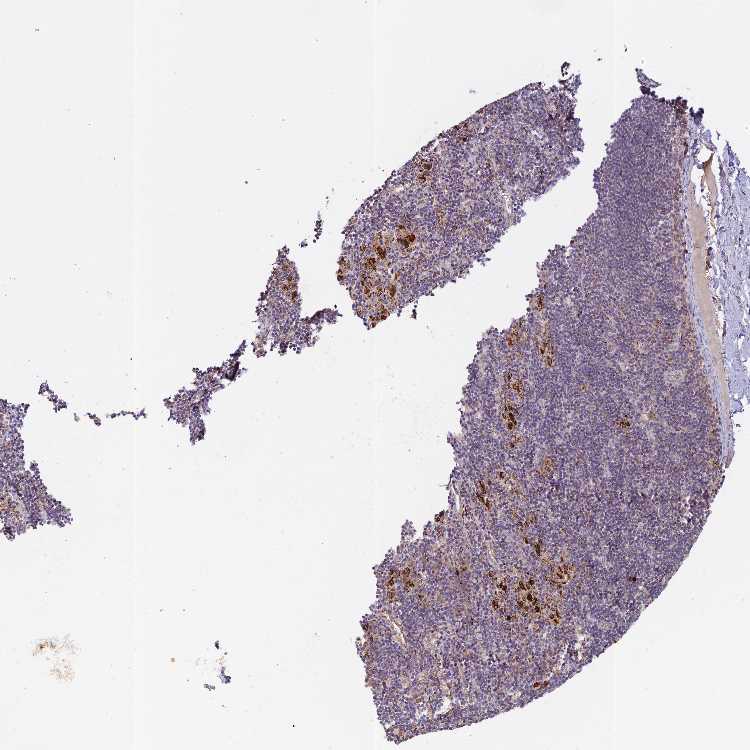

SOFT TISSUE 1 - Antibody stainingi

Antibody staining in the annotated cell types in the current human tissue is reported as not detected, low, medium, or high, based on conventional immunohistochemistry profiling in selected tissues. This score is based on the combination of the staining intensity and fraction of stained cells.

Each image is clickable and will lead to virtual microscopy that enables deeper exploration of all samples and also displays staining intensity scores, fraction scores and subcellular localization as well as patient and tissue information for each sample.

Antibody HPA042273

Fibroblasts Medium

Peripheral nerve Not detected